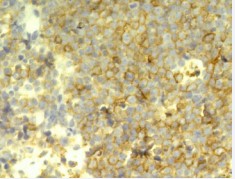

Immunohistological staining showed that the tumor cells were positive for L26, Bcl-2, CD3, CD20, CD79a and CD45RO (Figure 4),

Figure 4: Strongly positive staining for CD3 in tumor cells. (EnvisionTM×400).

(Figure 5)

Figure 5: Positive staining for CD20 in tumor cells. (EnvisionTM×400).

(Figure 6)

Figure 6: Positive staining for CD79a in tumor cells. (EnvisionTM×400).

but negative for CD8, S-100, CK and Tdt. The tumor was diagnosed as a B-cell malignant non-Hodgkin’s lymphoma. The CT of chest and abdomen and the endoscopic check of gastrointestinal showed no other mass. The endoscopic surgical procedure was done to remove the mass under general anesthesia with controlled hypotension. Then the patient was treated with combination of chemotherapy and radiotherapy. The patient was currently doing well, without evidence of recurrent disease.

The most important immunohistological marks of lymphoma are CD45RO, CD56, CD3 and TIA-l. The nasal cavity B-cell lymphoma, which marks are L26 and 4KB5, seldom suggest EBV infection. In our case, immunohistological staining showed that the tumor cells were positive for L26, Bcl-2, CD3, CD20, CD79a and CD45RO, but negative for CD8, S-100, CK and Tdt. The tumor was diagnosed as a B-cell malignant non-Hodgkin’s lymphoma. Some literature reported that CD56 and EBV-encoded RNA (EBER) 1/2 were the symbols of the bad prognosis. The people with those marks were not sensitive to the therapy and would relapse to die in short time [9].